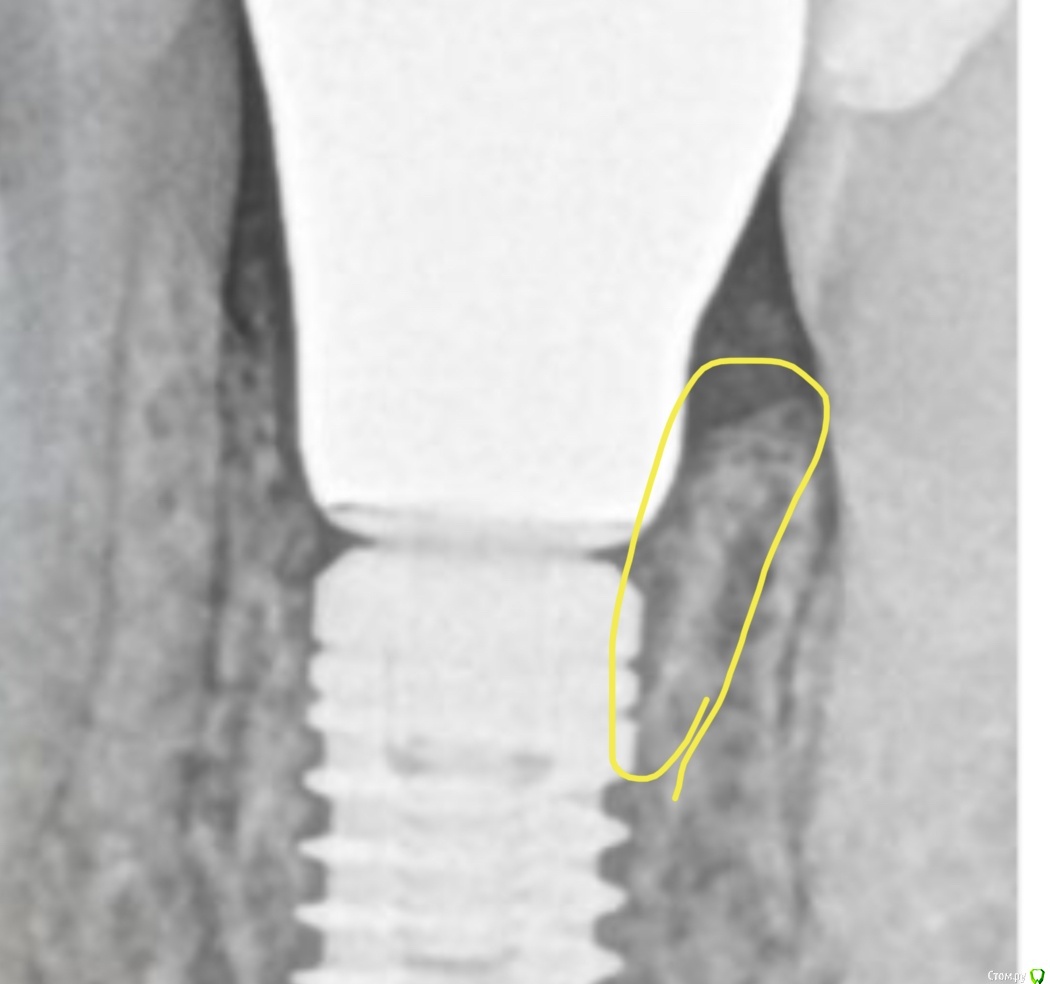

Irouil Опубликовано 19 декабря, 2020 Поделиться Опубликовано 19 декабря, 2020 Не подсекаю "у основания" (соединительнотканный этаж), ибо любые манипуляции в этой области считаю злом. Даже простые вынимания супраструктуры на этом уровне (привет one_abut_one_tume) считаются вредными, а уж повторное рубцевание в рамках этой логики с большой долей вероятности приведёт к резорбции крестального отдела. Кроме того, коническое соединение предполагает, что расширение супраструктуры (которое и несёт риски ишемии) должно всегда проходить только в рамках эпителиального этажа (не учитываем кривую ортопедию астры), то есть оклюзальнее демаркационной линии соединительнотканное-эпителиальное, а это делает все манипуляции с соединительнотканным прикреплением бессмысленными. 1 Ссылка на комментарий

колесников Опубликовано 20 декабря, 2020 Поделиться Опубликовано 20 декабря, 2020 (изменено) Вопрос с юбками интересный. Уступ не должен быть по крайней мере шире самого имплантата, иначе будет ишемия и т.д. - это нам подсказывает логика. Я и сам не люблю такие. Но исследования это опровергают) не знаю о каких Вы исследованиях и Линкявичюс по моему совсем иное проповедует,ни какое исследование не сможет подтвердить положительные свойства 1мм уступа для конической системы и субкрестальной позиции платформы. Десна отвоюет свои 2мм за счёт резорбции кости. Эти исследования могут быть верны только для имплантов с крестально и супракрестальной позицией. Изменено 20 декабря, 2020 пользователем колесников Ссылка на комментарий

kramer Опубликовано 20 декабря, 2020 Автор Поделиться Опубликовано 20 декабря, 2020 Эти исследования могут быть верны только для имплантов с крестально и супракрестальной позицией. Либо если заглубление не более 1 мм Ссылка на комментарий

колесников Опубликовано 21 декабря, 2020 Поделиться Опубликовано 21 декабря, 2020 (изменено) Хе-хе,так Вас вводят в заблуждение. Если у вас одномоментная имплантация с нагрузкой-тогда прокатит. Во всех остальных случаях-все будет плохо. Вот эта компактная кость появилась не после,а до имплантации. И конечно на кт будет выглядеть не так радужно ,как на прицельном. Если бы абатмент был высотой 3мм,на платформу наползла бы кость Изменено 21 декабря, 2020 пользователем колесников Ссылка на комментарий